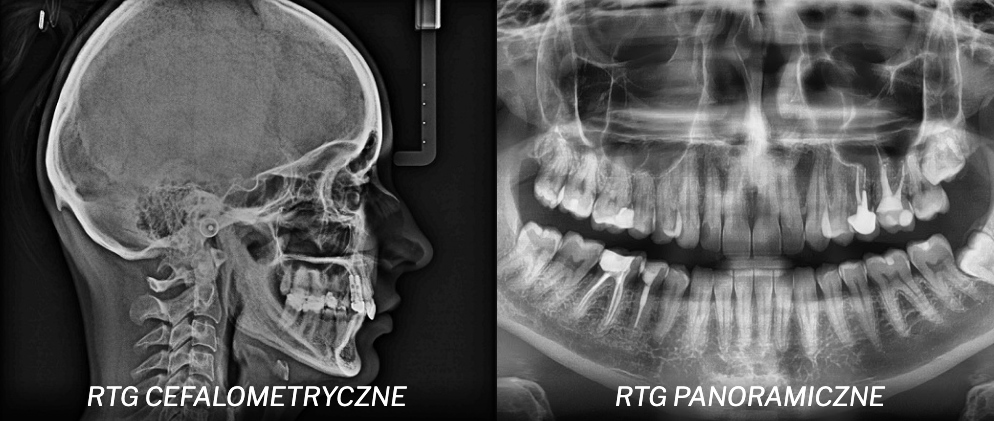

RTG panoramiczne i cefalometryczne

W IMDENTAL korzystamy również z jednego z najnowocześniejszych aparatów Carestream 8100, który umożliwia wykonywanie różnego rodzaju zdjęć w technologii cyfrowej:

- RTG panoramiczne (pantomogram) – obraz całego uzębienia, kości szczęk i zatok,

- RTG cefalometryczne – zdjęcia boczne czaszki, wykorzystywane szczególnie w ortodoncji,

- RTG przednio-tylne (PA) – przydatne w ocenie symetrii twarzoczaszki,

- RTG stawów skroniowo-żuchwowych – pomocne w diagnostyce zaburzeń stawu.